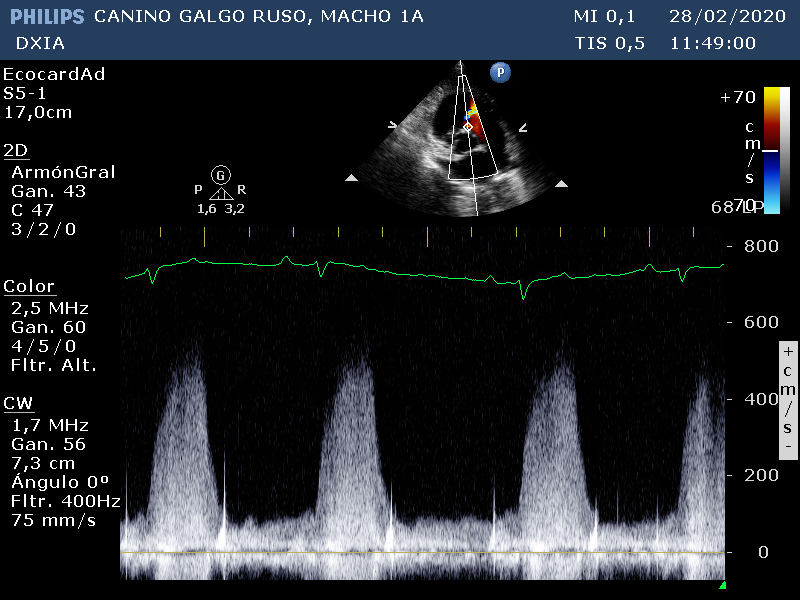

Doppler color en corte apical izquierdo de 4 cámaras. Se detecta defecto septo IV

Doppler color en corte en base cardíaca. Se detecta flujo turbulento compatible con decto del septo IV

Medición del flujo turbulento del defecto del septo IV (imagen 1)

Medición del flujo turbulento del defecto del septo IV (imagen 2)

- Defecto del septo IV de aproximadamente 4mm. No produce cambios hemodinámicos significativos.